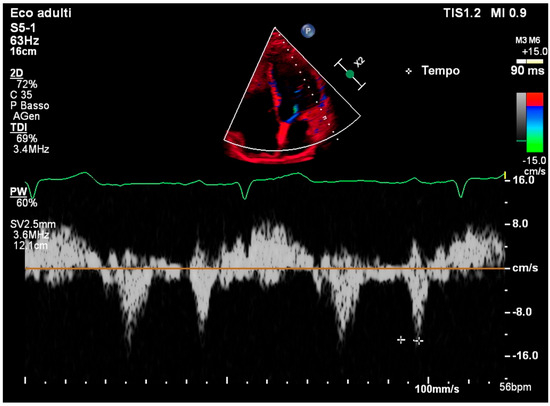

| TDI | Tissue Doppler Imaging |